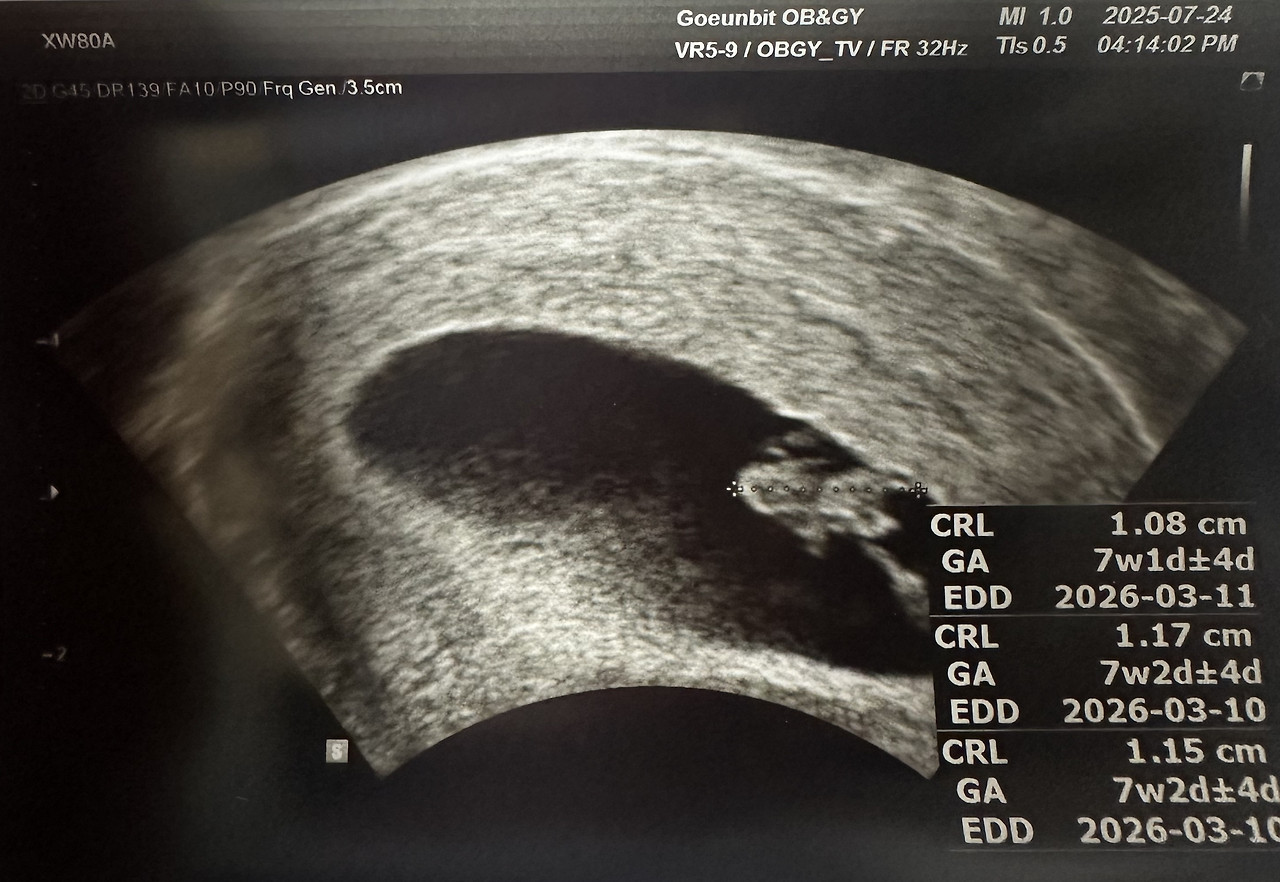

7주 차, 심장 소리를 듣다

드디어 아기의 심장 소리를 들었다.

7주 차 아기의 모습. 작지만 또렷하게 심장이 뛰고 있었다.